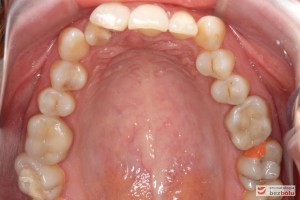

Pacjentka lat 26 zgłosiła się do gabinetu celem korekcji uśmiechu. Głównym zmartwieniem były problemy estetyczne, które znacznie wpływały na jakość życia pacjentki. Wykonano leczenie zachowawcze zębów oraz analizę cefalometryczną i analizę modeli diagnostycznych. Zaplanowano leczenie aktywne aparatem DAMON dla szczęki i żuchwy, które trwało 2 lata. Po fazie leczenia aktywnego rozpoczęto leczenie retencyjne z użyciem szyny tłoczonej dla szczęki i retainera stałego dla żuchwy.